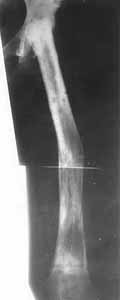

Ablation of upper part of hip crossing with lower/third in a Ilizarov's apparatus. Ablation of upper part of hip crossing with lower/third in a Ilizarov's apparatus.

Ablation of upper part of hip crossing with lower/third in a Ilizarov's apparatus.